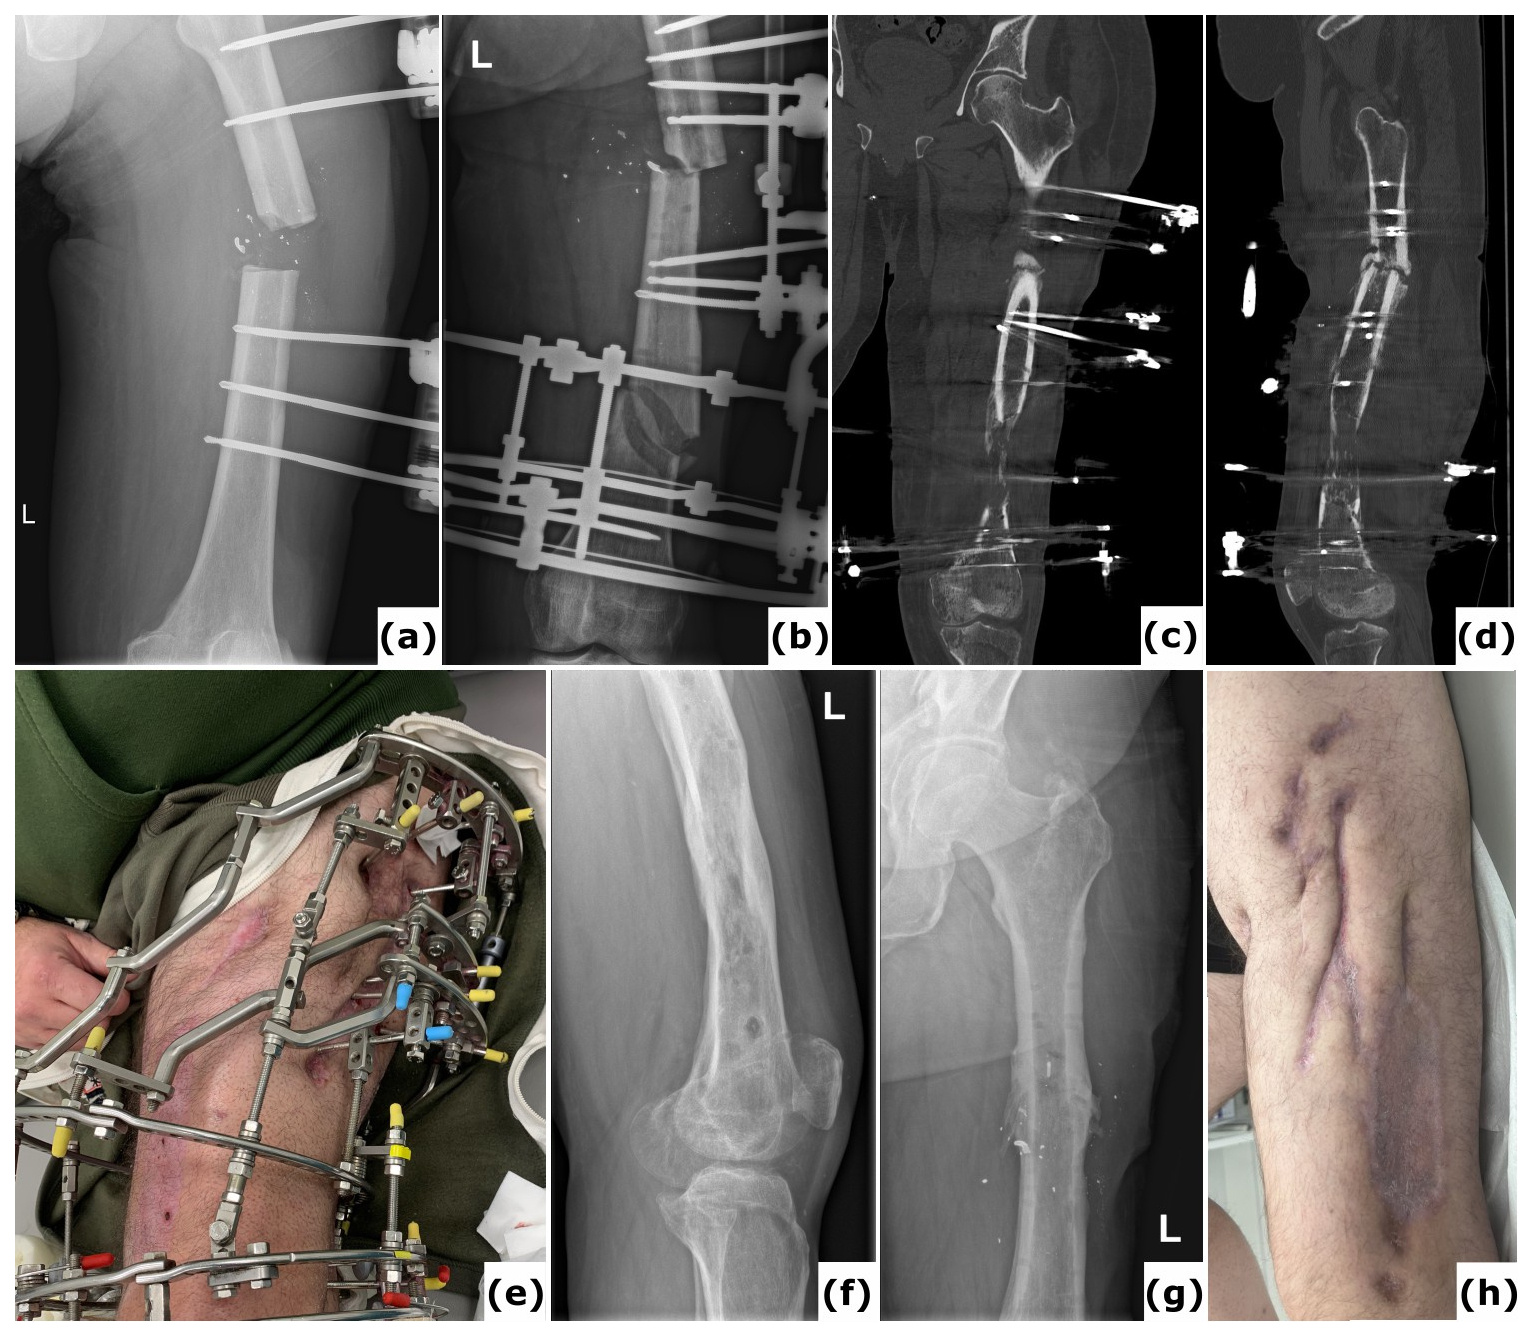

Figure 1A case of polymicrobial fracture-related infection (FRI) of the femur resulting from a gunshot injury is described. A 44-year-old polytrauma patient presented with multiple injuries, including a Gustilo-Anderson type III open femur fracture of the left lower limb. (a) The patient was transferred after initial stabilization, external fixation of the left femur, and several surgical wound debridements. (b) Anteroposterior radiograph of the left femur was taken following acute shortening, distal corticotomy, and lengthening. No cultures were collected during this surgery. (c–d) Computed tomography (CT) images of the left femur at 6 months show a persistent unhealed fracture site along with a distal distraction site that is not fully consolidated. Due to the presence of suggestive signs of FRI (local redness, swelling, and elevated serum inflammatory markers), local debridement of the fracture site was undertaken. Cultures grew Klebsiella pneumoniae and Enterococcus faecalis, for which the patient received systemic antibiotic therapy (6 weeks). (e) Clinical image of a classic ring fixator. (f–g) Lateral and anteroposterior radiographs after removal of the external fixator at 2 years demonstrate consolidation of the fracture and the distal distraction site. Because of continued pin site infections, local redness, and elevated serum inflammatory markers, the intramedullary canal was reamed and cultures were obtained, all of which were positive for Staphylococcus aureus. Again, the patient received systemic antibiotic therapy (6 weeks). (h) Clinical images of the lower limb 1 year after removal of the external fixator show significant scarring of the left thigh from the pin tracts. Knee flexion was limited to 10°. This case shows that long-term external fixation is not harmless and can be associated with several potential complications, such as joint contracture, scarring from the pin tracts, and severe chronic infections.